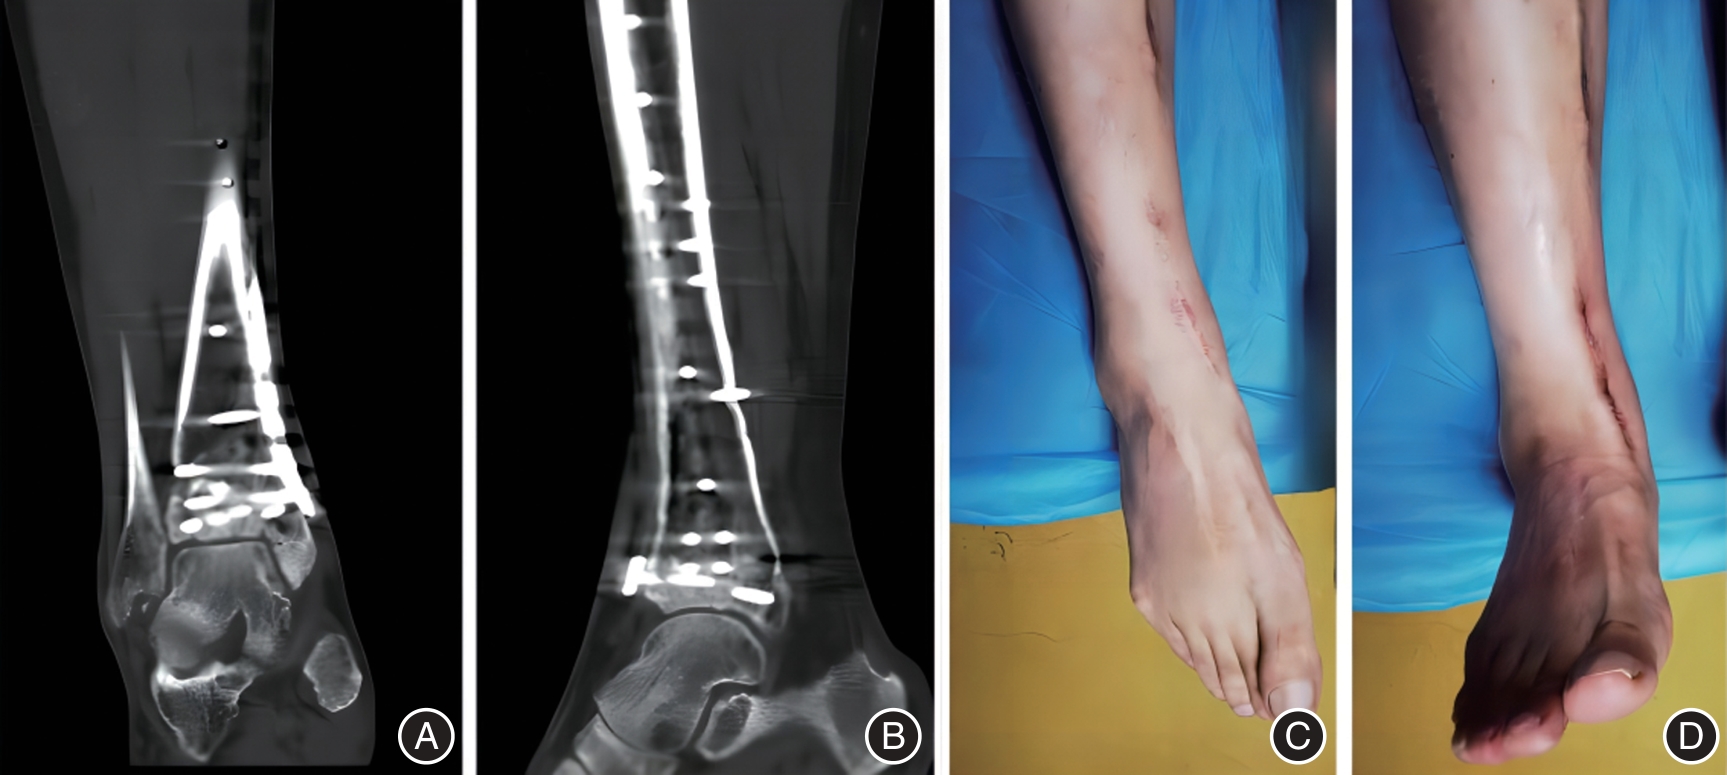

Youqiang ZHANG,Ling YAN,Wei LIAO,Guang WANG,Xiaoheng CHEN,Rui FAN,Zuwei. LIU. Study of modified anteromedial approach and preserves the superior extensor retinaculum for clinical effect of Pilon fracture[J]. The Journal of Practical Medicine, 2025, 41(3): 358-364.

21 | 胡远军, 成瑞萍, 史会明, 等. 改良前内侧入路治疗Ruedi-Allgower Ⅲ型Pilon骨折的疗效[J]. 实用骨科杂志, 2020,26(2): 124-127. |

22 | 周骅, 薛剑锋, 周朝, 等. 改良前内侧手术入路对Ruedi-Allgower Ⅲ型Pilon骨折的临床效果分析[J]. 浙江创伤外科, 2022,27(1): 139-140. |

23 | 黄绍飞,杨云平,黄海. 改良前内侧入路治疗复杂闭合性Pilon骨折的疗效[J]. 中华实验外科杂志, 2020,37(11):2121. |

24 | 付鲲鹏, 张晓敏, 赵艳霞, 等. 改良前内侧入路与前外侧入路对C3型Pilon骨折复位及疗效的影响[J]. 西南国防医药, 2020,30(8): 739-742. |